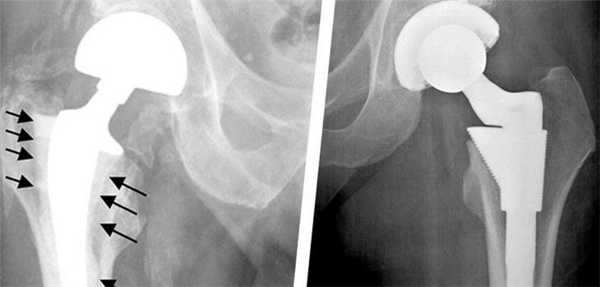

Методика доказала на практике свою эффективность, однако, даже самые совершенные технологии могут в долгой перспективе привести к возникновению осложнений. Нестабильность частей эндопротеза - самая часто встречающаяся патология, которая может вызвать нежелательные последствия и привести к необходимости повторной операции.

Можно выделить следующие признаки нестабильности эндопротеза тазобедренного сустава:

- Возникновение перманентной ноющей боли в суставе как во время ходьбы, так и в состоянии покоя. Зачастую болевые ощущения усиливаются ближе к ночи (во время сна).

- Потеря опоры для искусственного сустава.

- Общая слабость в нижних конечностях, быстрая утомляемость при ходьбе.

Все дело в том, что установленный имплантат влияет на движения тазобедренного сустава, как при тотальном эндопротезировании, таки при замене лишь части поврежденного сустава. В результате процесс восстановления костной ткани может замедлиться. Расшатывание ножки протеза в большинстве случаев приводит к развитию местного остеопороза. Таким образом, ограничивается подвижность самого эндопротеза.

К сожалению, современные научные и лабораторные исследования не смогли определить материал для протезов, которые бы не наносил абсолютно никакого вреда здоровью человека. В результате трения компонентов имплантата друг о друга мельчайшие частицы оседают в окружающих тканях, вызывая инфекционные процессы и отмирание тканей. Также может нарушится локальное кровообращение. Поэтому при появлении первых признаков расшатывания эндопротеза тазобедренного сустава следует немедленно обратиться за помощью к лечащему врачу.

Остеолиз

К образованию данного процесса может привести частичное или полное разрушение кости, которое наступает в результате взаимодействия компонентов протеза с живой тканью.

Перелом эндопротеза

Диагностика переломов протеза, которые периодически случаются, дает основания предположить следующие причины таких последствий. К ним относится:

- неправильный подбор индивидуального имплантата;

- чрезмерная или преждевременная высокая физическая активность пациента; пациента.